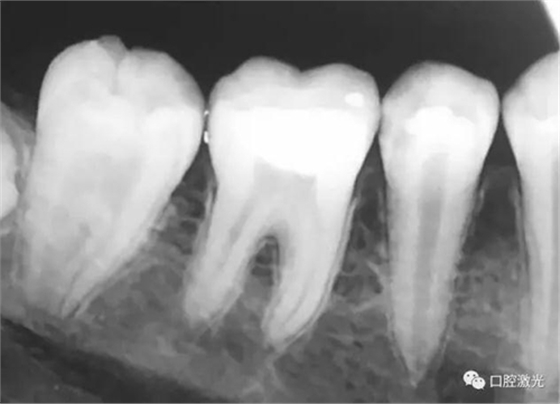

活髓理療治療結(jié)果令人滿意,沒有出血,也沒有出現(xiàn)碳化?;颊邲]有感受到不適并表示滿意。為了跟蹤激光輔助活髓切除術(shù)的治療效果,手術(shù)完成即刻和5周后分別拍攝了X光圖像。5周后的牙髓活性溫度測試也顯示陽性。

治療后即刻